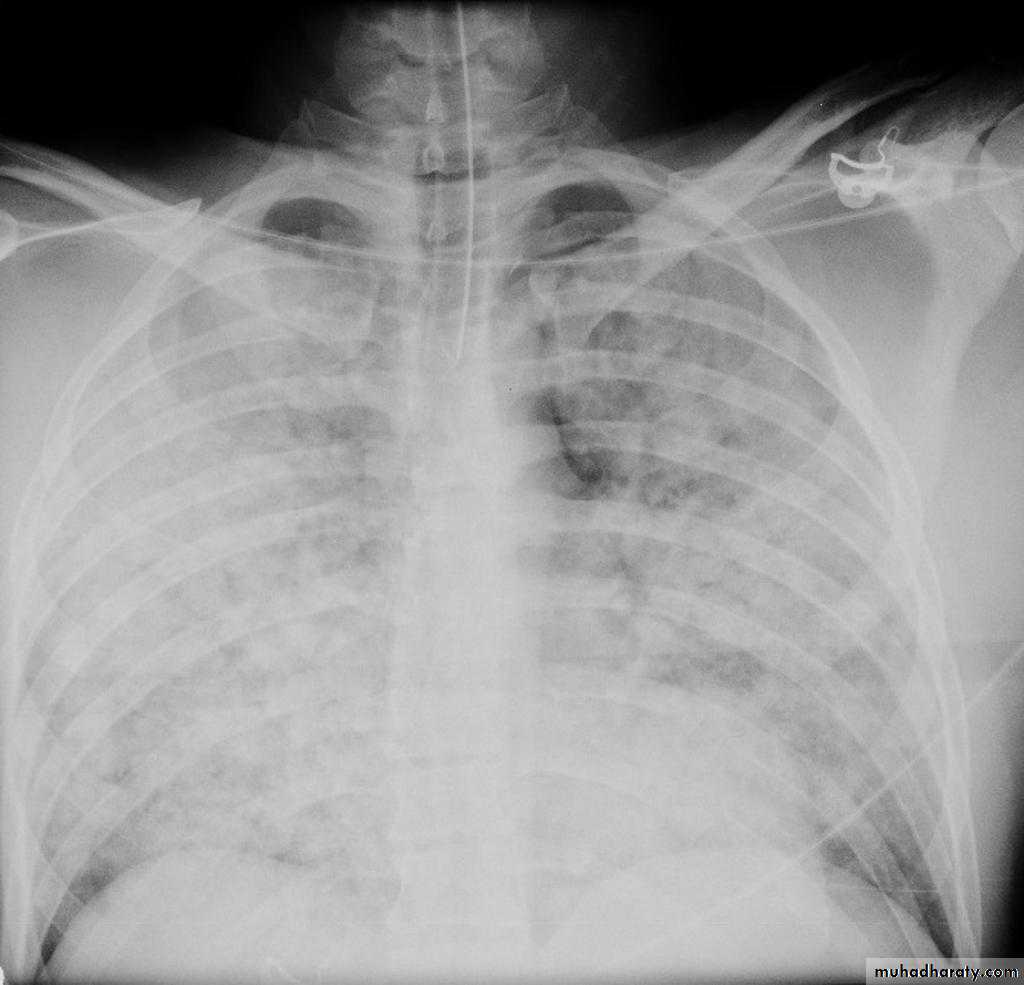

Pulmonary edema is a broad descriptive term and is usually defined as an abnormal accumulation of fluid in the extra-vascular compartments of the lung .

radiograph include if pressure > 25 mmHg the findings of :

1.cardiac size/cardio-thoracic ratio: useful for assessing for an underlying cardiogenic cause or association2.Pulmonary Alveolar edema: bat wing pulmonary opacities

3.Pulmonary interstitial edema: presence of peri-bronchial cuffing///septal lines: Kerley lines become more prominent4.pleural effusions

5.Central pulmonary venous engorgement

6.pulmonary blood flow distribution& upper lobe pulmonary venous diversion

Alveolar pulmonary edema